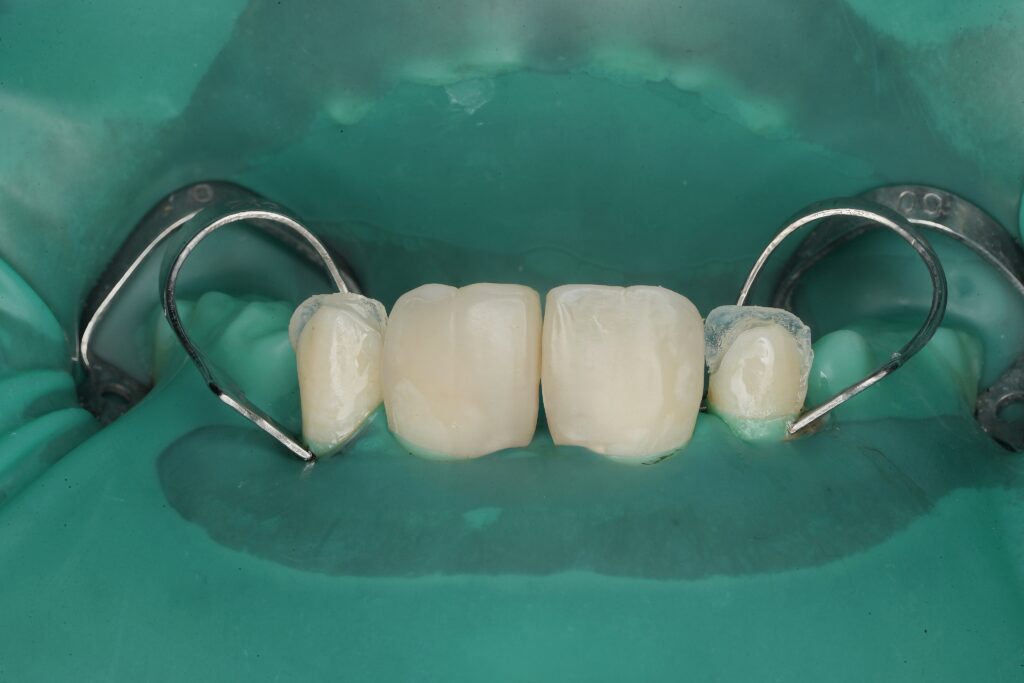

Step 4 – Emergence Profile Development

One of the most critical steps in diastema closure is biological contour control.

- Proximal build-up performed incrementally

- Emergence profile designed to support papilla without overhang

- Contact point positioned strategically to prevent black triangles

This step prevents periodontal compromise and ensures long-term papillary stability.

Outcome

- Diastema closed harmoniously

- Midline visually centered

- Gingival architecture respected

- No over-contouring or periodontal compromise

- Immediate aesthetic enhancement

The patient achieved a natural smile without orthodontic intervention, while enamel preservation remained the primary objective.